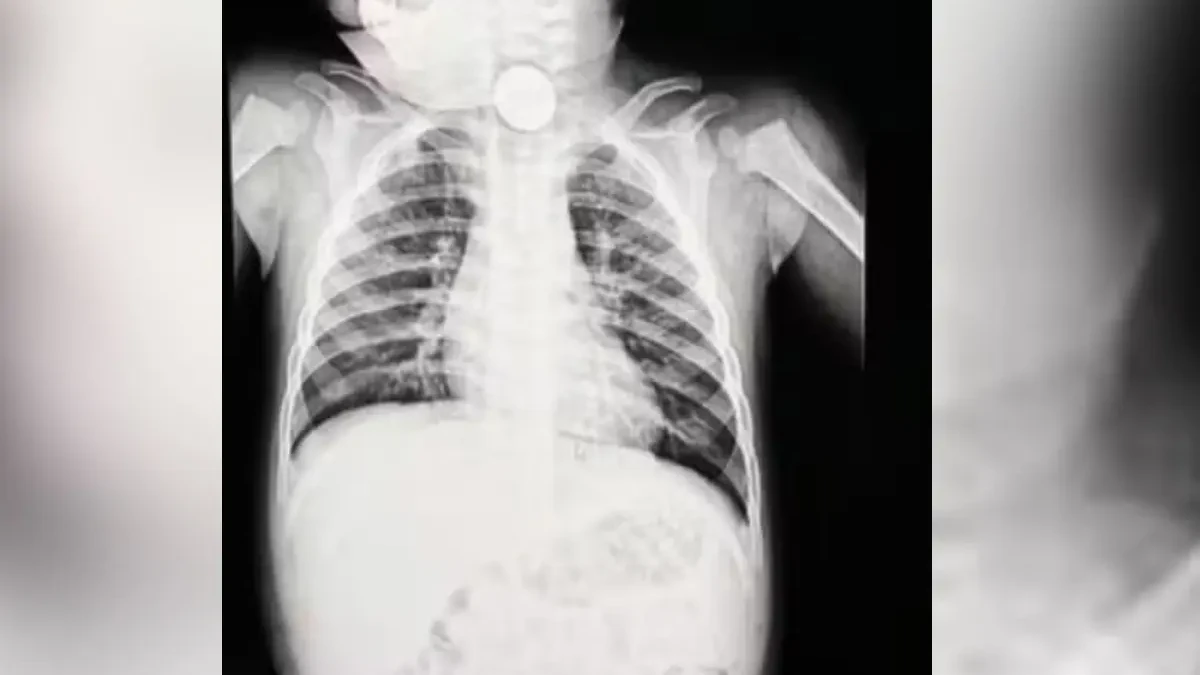

Exames de imagem revelaram a presença de uma bateria tipo botão alojada no esôfago do menino. Inicialmente considerado um objeto inofensivo, o item foi diagnosticado como uma bateria de brinquedo apenas após nova avaliação médica. A criança permaneceu cerca de 12 horas com a bateria no corpo antes de ser submetida a uma endoscopia para retirada. Durante o procedimento, os médicos identificaram sinais de necrose no esôfago e risco de perfuração, uma complicação que pode evoluir para uma infecção generalizada se não tratada rapidamente.